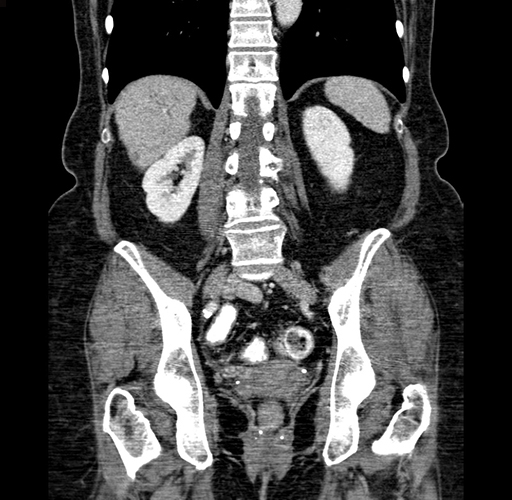

Pre-Chemo: Coronal Venous

Coronal Venous